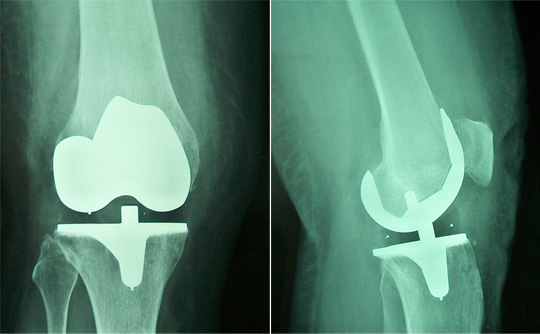

Surgical procedure involves replacing the arthritic surfaces of the knee with metal and plastic implants.

A total knee arthroplasty is composed of a femoral cap, a tibial tray and an insert made of polyethylene.

Fixation of the componets can be achieved with or without bone cement.

X ray and example of an implanted total knee arthoplasty.